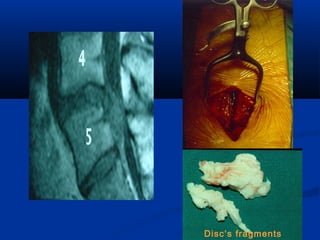

Disc’s fragments

Μετά - Δισκεκτομή

Η αντίσταση σε :

• αξονική φόρτιση  30%

• στρέψη  50%

• κάμψη  50%

• έκταση  70%